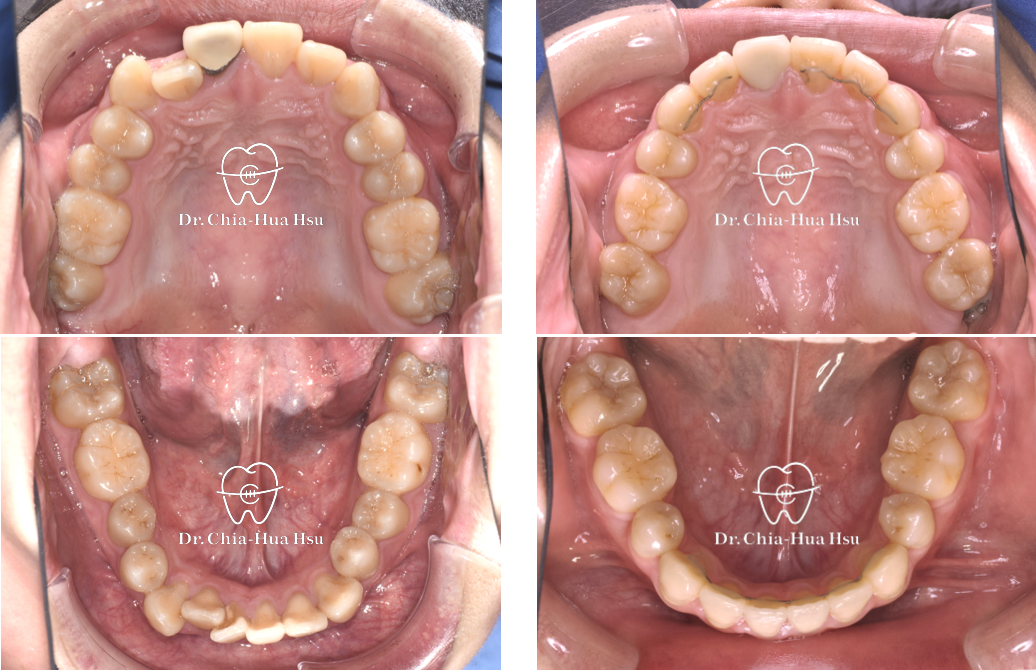

前牙錯咬、齒列擁擠

成人矯正 | ⾦屬矯正 | 拔牙治療

• 病患主訴:牙齒凌亂擁擠、笑起來不好看。

• 問題分析:患者是標準的骨骼一類咬合(Skeletal Class I)伴隨齒列擁擠以及前牙錯咬。

• 治療方式:拔除四顆小臼齒,使用傳統金屬矯正器將牙齒排列整齊、咬合緊閉。

• 治療時間:1 年 10 個月。

• 治療結果:齒列排齊,笑容更燦爛。

治療前

治療後